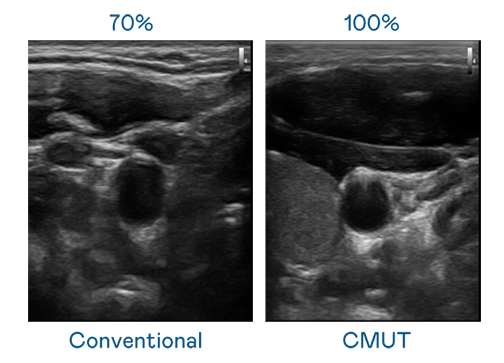

CMUT 技术是一种用电容式微机电元件来产生超音波讯号的技术。与传统 PZT 压电式技术相比,CMUT 频宽增加 30%,更宽频的超音波讯号让影像解析度大幅提升,是实现高影像品质医疗超音波扫描、促进精准医疗发展的关键技术。

超音波影像的解析度高低,首先取决于探头能发出的讯号频宽。龙源国际 CMUT 可提供高清晰的超音波讯号,提供高频宽、高灵敏度、影像纹理细节更高的超音波影像,协助医护人员缩短影像判读时间及利用精准的医疗影像进行诊断。